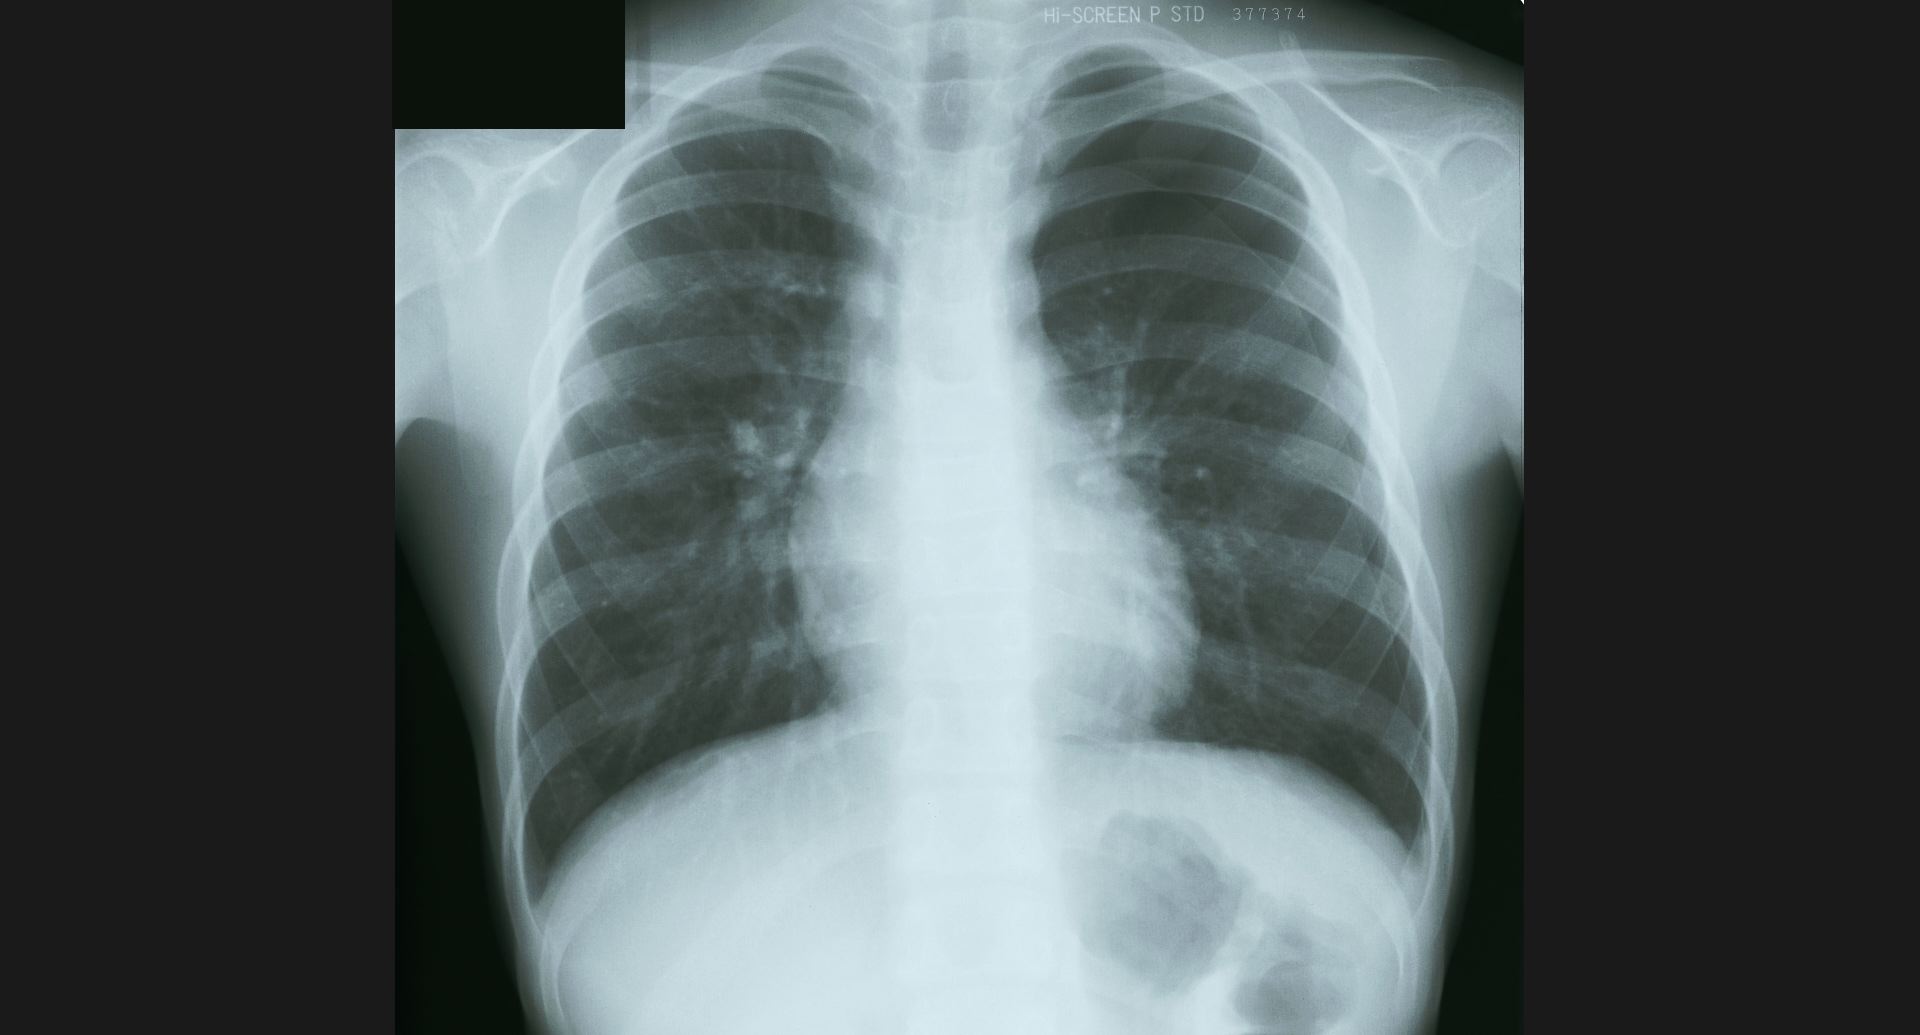

fig.1(117KB)

:Alveolar microlithiasis細かい肺病変、air bronchogram。